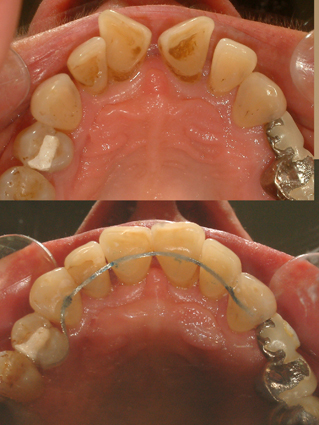

Απεικονίζονται οι διάφοροι κινητοί και ακίνητοι μηχανισμοί συγκράτησης του αποτελέσματος της ορθοδοντικής θεραπείας

Μετά από την ολοκλήρωση της ενεργού φάσης της ορθοδοντικής θεραπείας, πάντοτε διατηρείται κάποια (διαφορετική για κάθε περίπτωση) πιθανότητα για υποτροπή της θεραπευμένης ορθοδοντικής ανωμαλίας. Οι ιστοί του στόματος και ειδικότερα εκείνοι που εντοπίζονται γύρω από τα δόντια, σε γενικές γραμμές διαθέτουν ισχυρή μνήμη και μέσω αυτής, επιδιώκουν συνεχώς την επαναφορά των δοντιών στην αρχική τους θέση, ακόμη και μετά την ολοκλήρωση της ορθοδοντικής θεραπείας. Για το λόγο αυτό, η ορθοδοντική θεραπεία δεν πρέπει να θεωρείται ότι ολοκληρώθηκε μετά την αφαίρεση των ορθοδοντικών μηχανισμών. Ο ασθενής από την πλευρά του, πρέπει να κατανοήσει την ιδιαίτερη σημασία που έχει η φάση της συγκρατήσεως του θεραπευτικού αποτελέσματος, κατά την οποία πρέπει να ακολουθεί πιστά τις οδηγίες του ορθοδοντικού του, ώστε το αποτέλεσμα της θεραπείας να είναι σταθερό. Ως ένας αδρός κανόνας, ισχύει ότι, όσο μεγαλύτερη και βαρύτερη είναι η αρχική ορθοδοντική ανωμαλία, τόσο μεγαλύτερο διάστημα θα απαιτηθεί να διαρκέσει η συγκράτηση του θεραπευτικού αποτελέσματος. Με τα κατάλληλα κατά περίπτωση συγκρατητικά μέσα, τα δόντια διατηρούνται παθητικά στις νέες τους θέσεις, στις οποίες έχουν μετακινηθεί με την ορθοδοντική, για το απαραίτητο χρονικό διάστημα, ώστε να αποκτήσουν "νέα μνήμη" και να σταθεροποιηθούν στις θέσεις αυτές. Για τον ίδιο λόγο, μετά την ορθοδοντική θεραπεία, πρέπει πάντοτε να αξιολογείται η φάση διαπλάσεως και η διεύθυνση ανατολής (δηλαδή της εμφάνισής τους στο στόμα) των φρονιμιτών (ή σωφρονιστήρων). Αν και δεν έχει αποδειχθεί, εν τούτοις υποστηρίζεται από ορισμένους ερευνητές, ότι οι φρονιμίτες, προκειμένου να αποκτήσουν τον απαραίτητο χώρο στις οπίσθιες περιοχές του στόματος, μπορούν να ωθήσουν τα πρόσθια δόντια προς τα εμπρός, με την ενδογενή δύναμη που διαθέτουν και έτσι να προκαλέσουν εκ νέου συνωστισμό (δευτερογενώς) των προσθίων δοντιών. Έτσι, τις περισσότερες φορές όπου ο διαθέσιμος χώρος δεν κρίνεται αρκετός για την ανατολή των φρονιμιτών, τότε δίνεται από τον ορθοδοντικό, η εντολή για άμεση εξαγωγή τους ακόμα και σε πρώιμη φάση διάπλασής τους, και μάλιστα πριν εμφανισθούν στο στόμα.